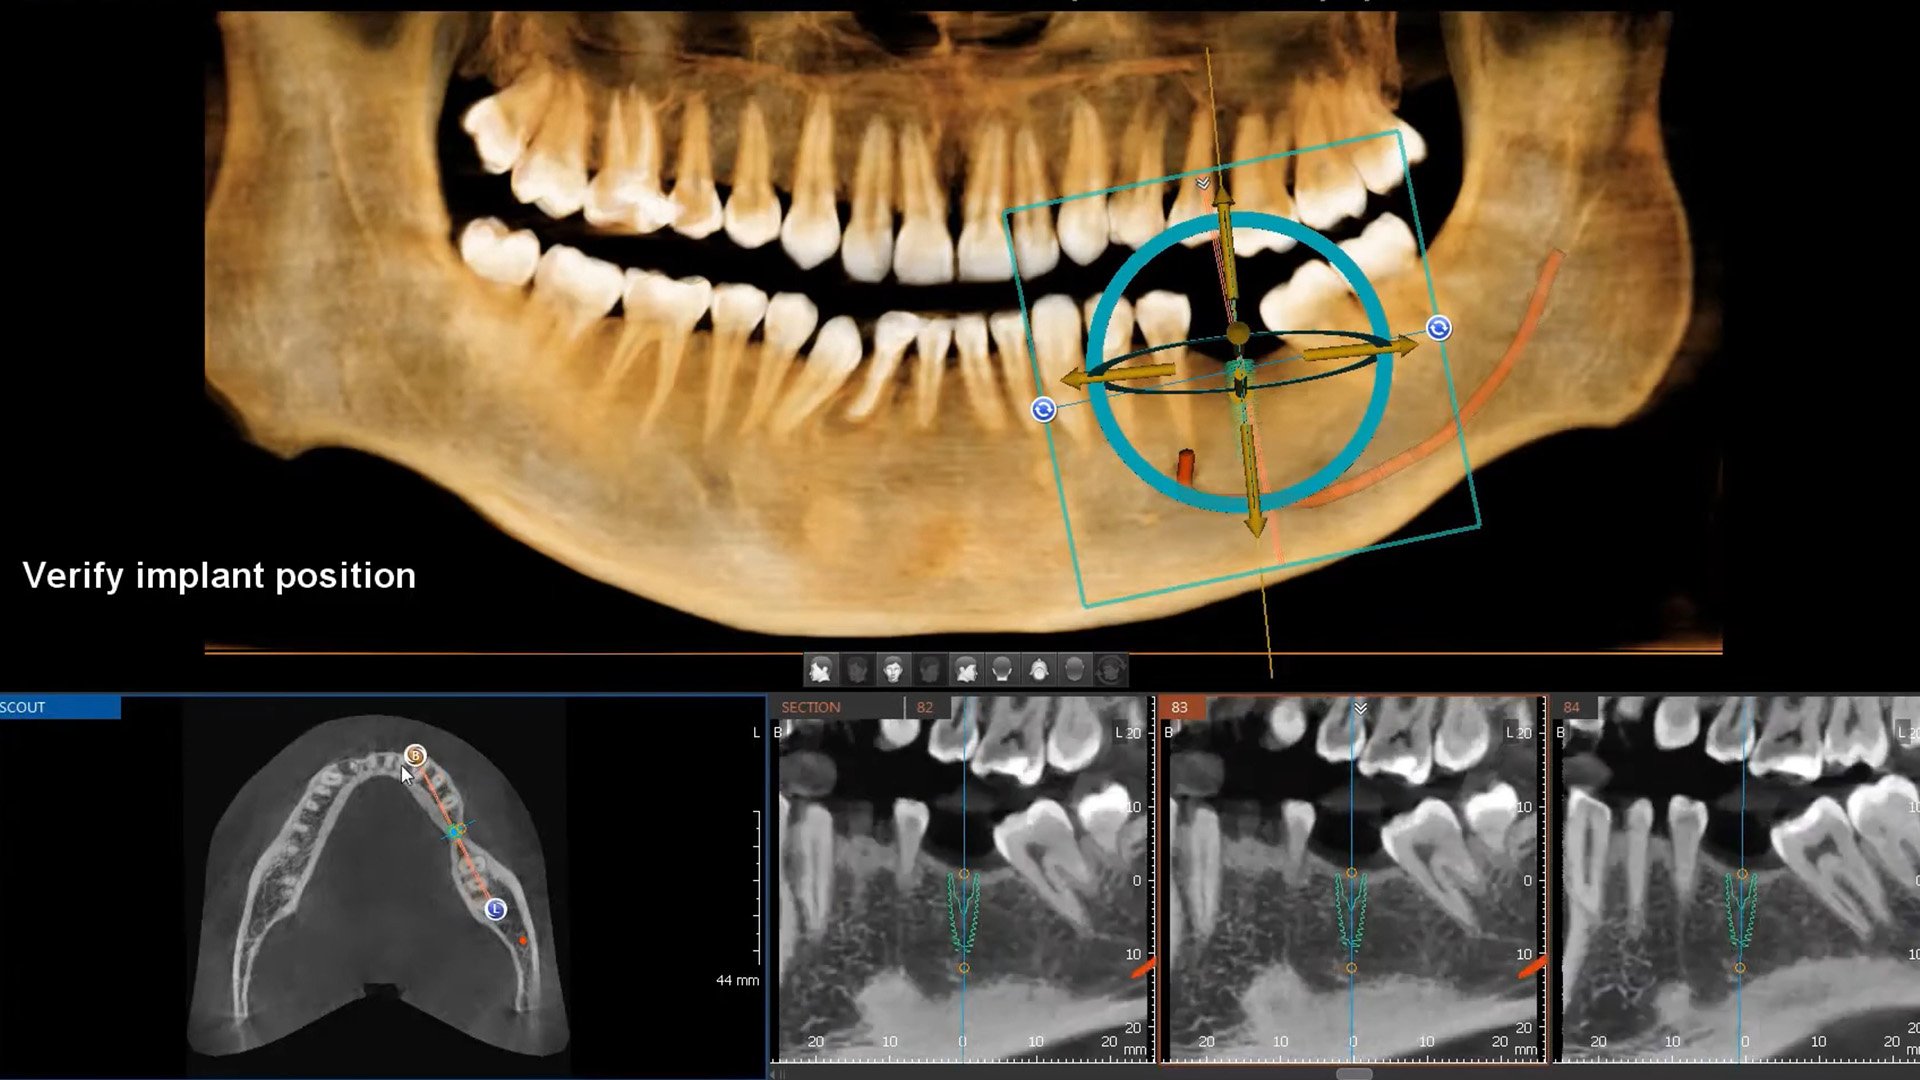

+ Hansmart – Lên kế hoạch điều trị an toàn, duy trì kết quả dài lâu: Dữ liệu từ CT cone beam và dữ liệu scan mẫu hàm kỹ thuật số được tích hợp vào Hansmart giúp bác sĩ tầm soát cấu trúc xương hàm, mạch máu, dây thần kinh, khảo sát mật độ xương chất lượng xương, cấu trúc vi tế từ đó lựa chọn vị trí đặt implant an toàn, tính toán độ sâu, góc nghiêng và cân bằng theo ba chiều không gian giúp răng sứ được phục hình chuẩn khớp cắn khôi phục chức năng thẩm mỹ và ăn nhai giúp răng implant chịu lực tốt, duy trì kết quả dài lâu.

+ Hanguide – Đặt implant chính xác vị trí đã được giả lập và không đau

Công nghệ giúp định vị mũi khoan chính xác trùng khớp với vị trí được giả lập. Đồng thời ứng dụng công nghệ từ tính, nén ép lên mô xương tạo lỗ chờ implant nên quá trình phẫu thuật nhẹ nhàng, không sưng đau sau phẫu thuật.